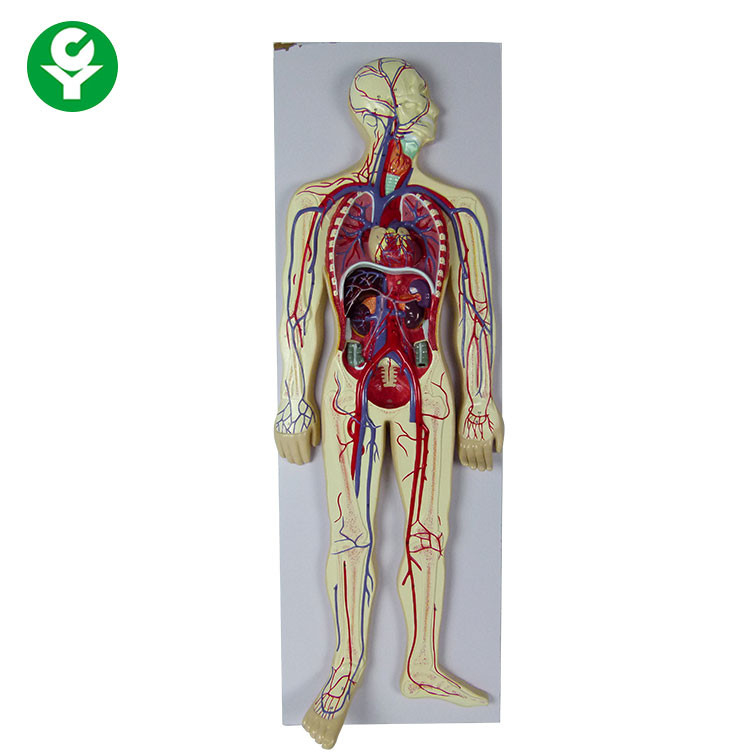

วันหัวใจโลก | Oldeenglishconsortium รูปแบบการสอนแบบระบบไหลเวียนโลหิตของมนุษย์ / การสอนแบบจำลองการไหลเวียนโลหิต

รูปแบบการสอนแบบระบบไหลเวียนโลหิตของมนุษย์ / การสอนแบบจำลองการไหลเวียนโลหิต รูปแบบการสอนแบบระบบไหลเวียนโลหิตของมนุษย์ / การสอนแบบจำลองการไหลเวียนโลหิต

รูปแบบการสอนแบบระบบไหลเวียนโลหิตของมนุษย์ / การสอนแบบจำลองการไหลเวียนโลหิต อวัยวะภายในและระบบไหลเวียนโลหิตของหญิงสาว ภาพประกอบสต็อก – ดาวน์โหลดรูป …

รูปแบบการสอนแบบระบบไหลเวียนโลหิตของมนุษย์ / การสอนแบบจำลองการไหลเวียนโลหิต รูปแบบการสอนแบบระบบไหลเวียนโลหิตของมนุษย์ / การสอนแบบจำลองการไหลเวียนโลหิต

รูปแบบการสอนแบบระบบไหลเวียนโลหิตของมนุษย์ / การสอนแบบจำลองการไหลเวียนโลหิต ฟิตเพิ่มเกรด ชีวะ ม.ปลาย – หัวใจเเละระบบหมุนเวียนเลือด – Dek-D’s School

แบบจำลองระบบหมุนเวียนโลหิตของมนุษย์ – EnterCenterShop ระบบหมุนเวียนโลหิต